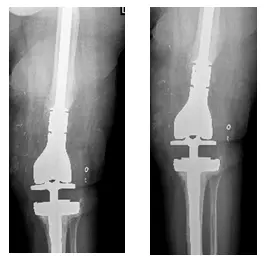

X-Rays show left knee intraoperative changes including long stem femoral and tibial prosthesis

X-Rays show left knee TKA one year post-operatively

Upon follow-up patient complains of no pain, has a good range of motion, is weight-bearing as tolerated, and has been doing well subsequently.